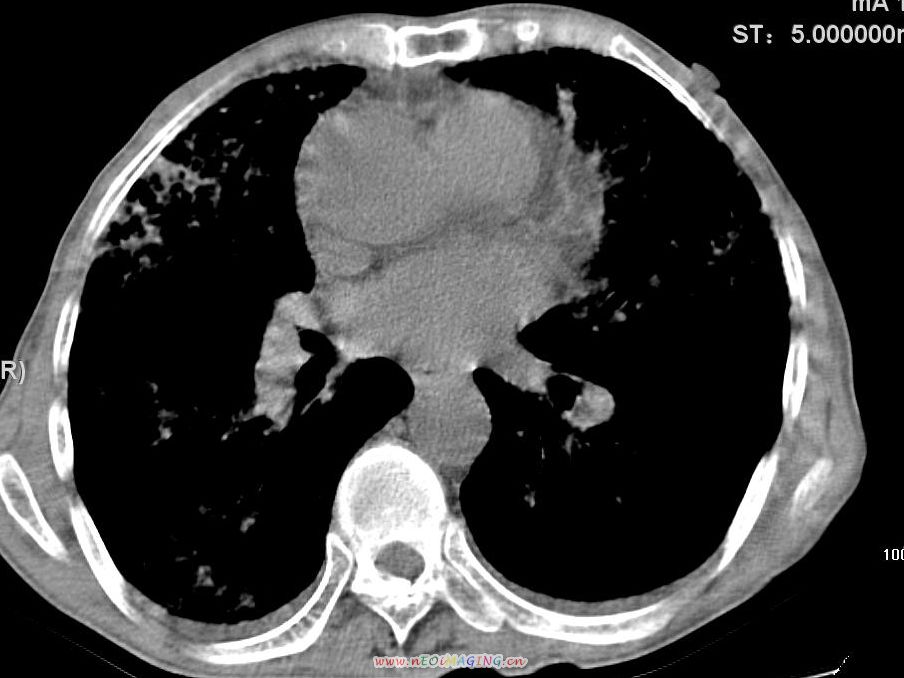

患者咳嗽月余,高热数天,咳黄色稍脓痰。

双肺野分布多个小结节状高密度影,其内散在斑片状模糊影,气管。支气管通畅,纵隔内淋巴结钙化,胸膜局限性增厚粘连,胸腔少量积液。结合病史考虑结核并感染的可能性大,胸膜炎并积液。肺泡癌待排。

纵隔内见钙化的淋巴节,上肺见钙化灶,双肺均匀弥漫分布小结节影,边缘较清楚,能不能考虑是在矽肺的基础上并发的结核和感染,请详细了解病史结合临床.

高热数天,咳黄色稍脓痰,肯定应该有急性化脓性感染,左上叶舌段及右肿叶可见多量斑片状及支气管气像,首先考虑肺部感染合并血型播散性肺脓肿(脓肿为早期改变),其次不排除有肺泡癌,第三不排除结核,建议治疗后复查